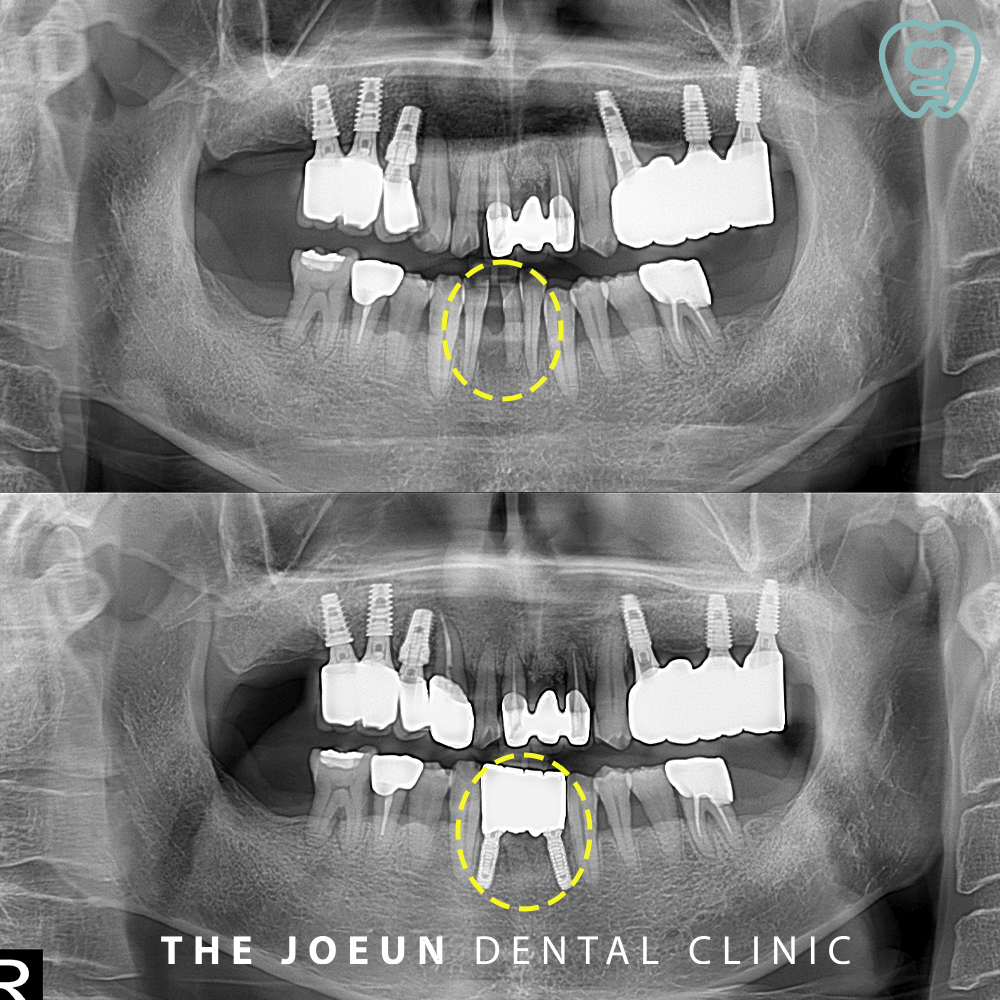

오늘은 심한 치주염으로 인해 자연적으로 발치된 앞니를 즉시 대실역앞니임플란트 식립을 진행하신 환.자분을 소개해 드리도록 하겠습니다. 환.자분께서는 아래 앞니가 빠지셨다며 내원해 주셨는데요.

심한 치주염으로 인해 아래 앞니가 빠진 것으로 판단되었고, 인접해 있는 치아들도 모두 심한 치주염으로 치아의 동요도가 3도로 보여 많이 흔들리고 있어 장기적인 예후가 좋지 않아 발치 후 대실역앞니임플란트 식립 계획을 수립하였습니다.

예후가 좋지 않던 인접 치아들을 발치한 후 즉시 임플란트 식립을 진행한 뒤, 임시 틀니까지 제작해 드렸는데요.

잇몸 상태를 고려하여 기존의 잇몸뼈와 인공치근이 충분히 단단하게 융합될 수 있도록 묻어둔 뒤, 2차 수술을 진행하여 힐링 어버트먼트를 체결한 모습인데요.

2023년 9월 21일 발치 후 즉시 임플란트 식립을 진행한 지 약 3개월여 만인 12월 27일 최종 보철물까지 완성할 수 있었는데요.